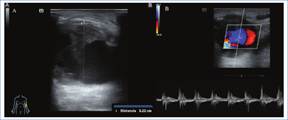

Pseudoaneurisma

Es una cavidad situada por fuera de las estructuras vasculares, sin pared propia, que en su mayoría se producen en FAV protésicas como consecuencia de punciones repetidas que lesionan las paredes de la prótesis1,3,4.

La ecografía permite diferenciarlo del hematoma al presentar flujo interno en la evaluación Doppler color, que se puede presentar de tipo turbulento (Fig. 6) o con un patrón típico en yin-yang. Adicionalmente se observa el signo del vaivén o de entrada-salida en el cuello del pseudoaneurisma en la evaluación espectral, caracterizada por el retorno de la sangre del saco aneurismático a la luz del vaso durante la diástole3,5.

Con menor frecuencia puede presentarse en fístulas nativas en relación con los sitios de punción, pudiendo afectar a la arteria aferente, la anastomosis o la vena eferente. La ecografía Doppler resulta de utilidad para su diagnóstico y además permite identificar la presencia de trombosis parcial o total (Fig. 7), así como reconocer estenosis proximales a los pseudoaneurismas que faciliten su formación.